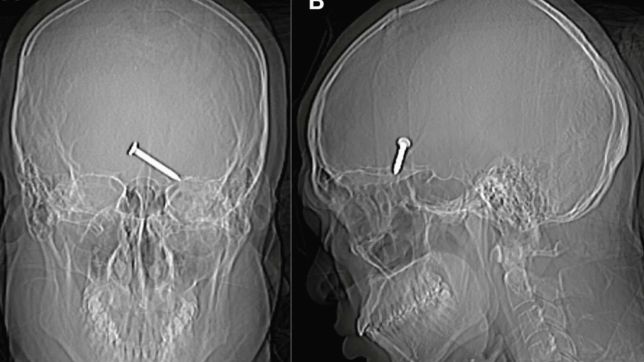

Um raio-x do crânio mostrou que o prego de três centímetros havia se alojado no cérebro do malasiano. Parte do crânio dele foi dilacerada pelo impacto. Apesar da gravidade do ferimento, o homem apresentava bons sinais vitais.